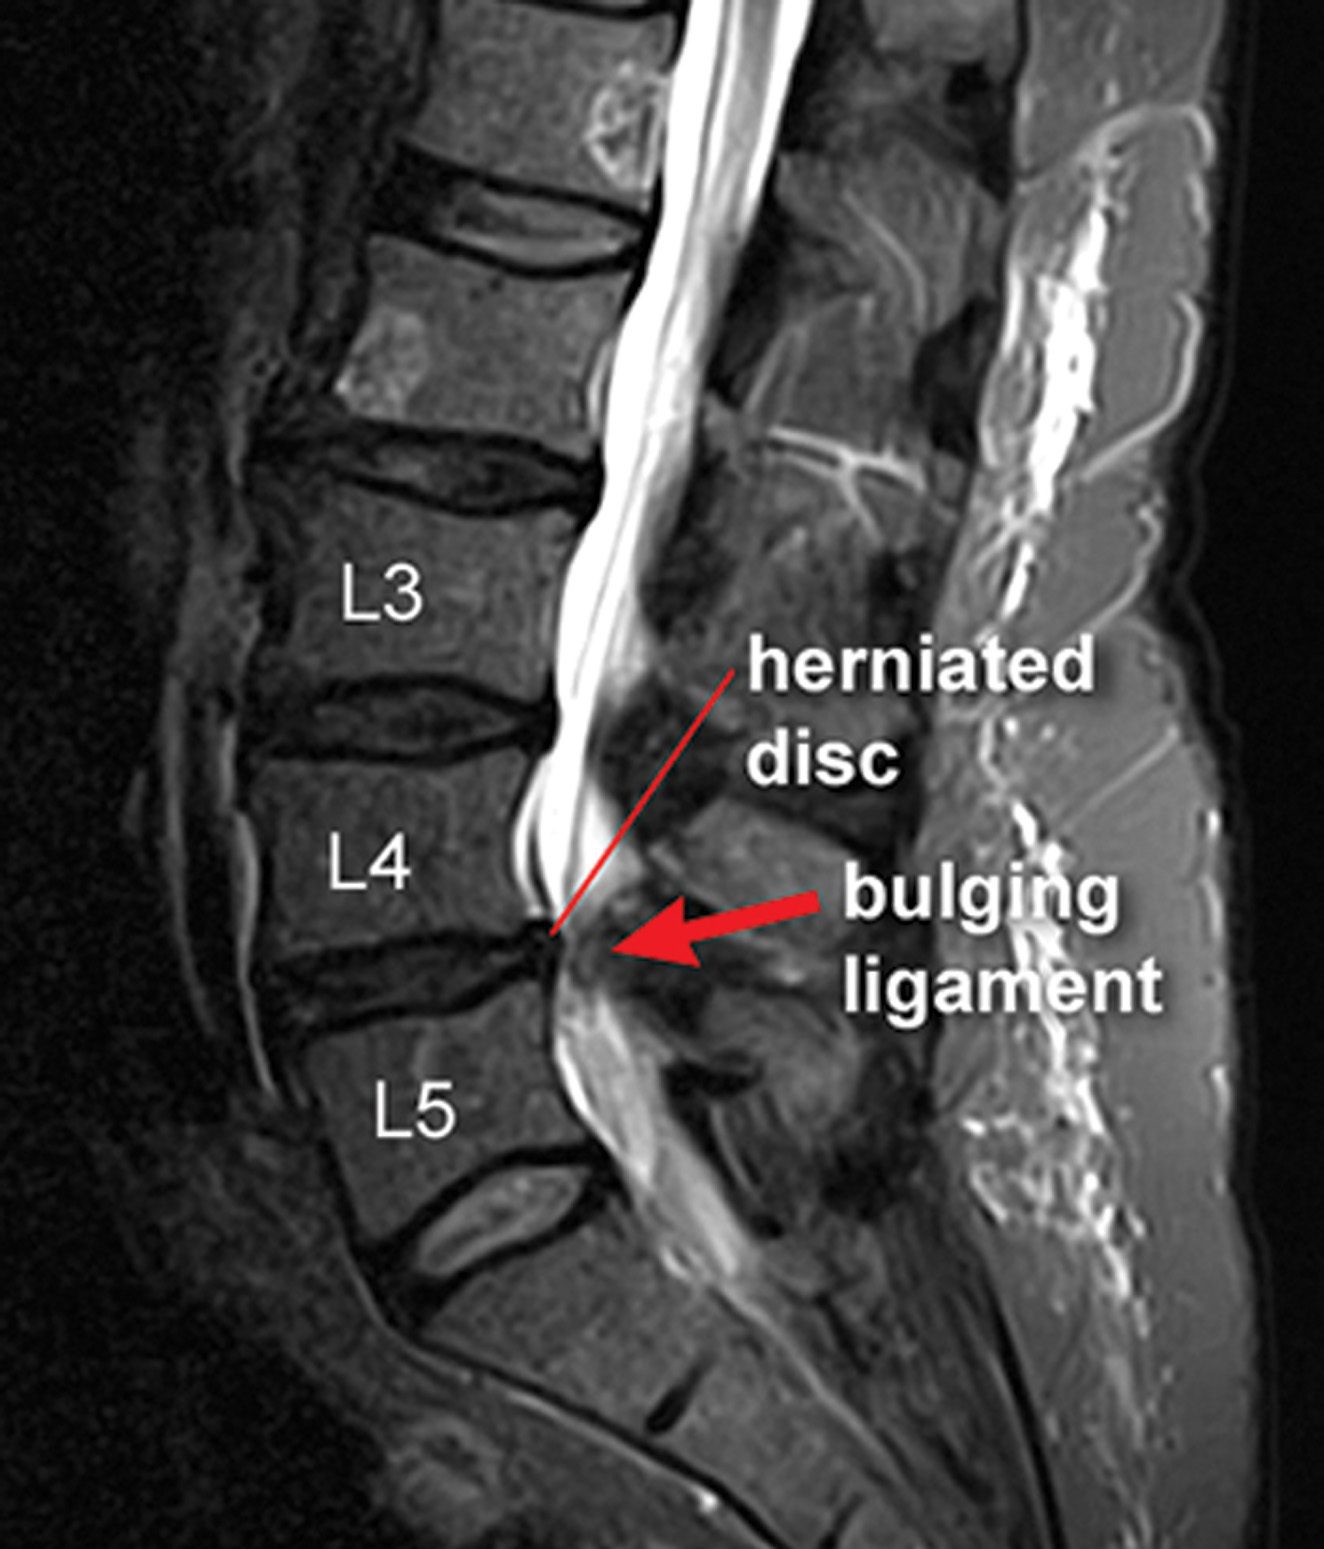

What is a Herniated Disc MRI, and When Do You Need It? Dr. Kevin Pauza Can You Sleep On Your Back With Herniated Disc sleeping on your back or side is the best option if you have a herniated disc in your neck. how to sleep with a herniated neck disc. You will be able to choose the position that you want to sleep when you have a neck disc herniation. you can have a slipped disc in any part of. Can You Sleep On Your Back With Herniated Disc.